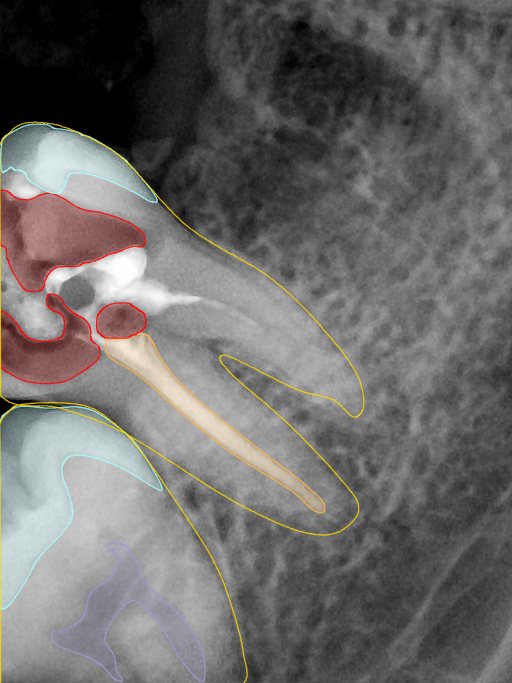

CR/DR 牙齿分割阶段记录

当前进展

- 完成了 CR/DR 牙齿相关分割训练

- 当前结果已经达到阶段预期,但仍有细节问题需要继续处理

相关测试

遇到的问题

- 训练过程中出现过 mask 下移问题

- 部分结果会出现 box 填充异常

- mask 边缘仍然有比较明显的锯齿感

参考

第二版算法问题测试

| 第一版 | 第二版 | 是否解决 | |

|---|---|---|---|

![]() | ![]() ![]() 边角识别有问题 龋齿识别不全 牙髓识别不全 | ![]() | 解决 |

![]() | ![]() 边角识别有问题 识别信息有误 自查(牙冠识别不全) | ![]() | 解决 |

![]() | ![]() ![]() 边角识别有误 大范围填充识别遗漏 | ![]() | 解决 |

![]() | ![]() 识别信息不全 | ![]() | 解决 |

![]() | ![]() ![]() 边角问题 牙胶识别不全 牙冠识别不全 | ![]() | 解决 |

![]() 换图片 | ![]() | ![]() 牙冠部分稍微白了一些就识别成小范围修补,部分判断异常 | 部分解决,修复类略敏感,牙冠部分稍微白了一些就识别成小范围修补,部分判断异常。 |

![]() | ![]() ![]() 牙冠识别不全 牙髓不全 根尖炎龋齿识别有误 | ![]() | 解决 |

![]() | ![]() | ![]() | 解决 |

![]() 换图片 | ![]() | ![]() | 解决 |

![]() | ![]() 牙冠识别有误 | ![]() | 解决 |

![]() 换图片 | ![]() ![]() 边角识别有误 | ![]() 修复类敏感 | 部分解决,图像过白,导致修复类判断异常。 |

![]() 换图片 | ![]() 牙冠识别不全 | ![]() 修复类敏感 | 部分解决,图像过白,导致修复类判断异常 |

结论:修复类出现了不鲁棒的情况,后续需要加入轮廓的扩充数据进行增强。